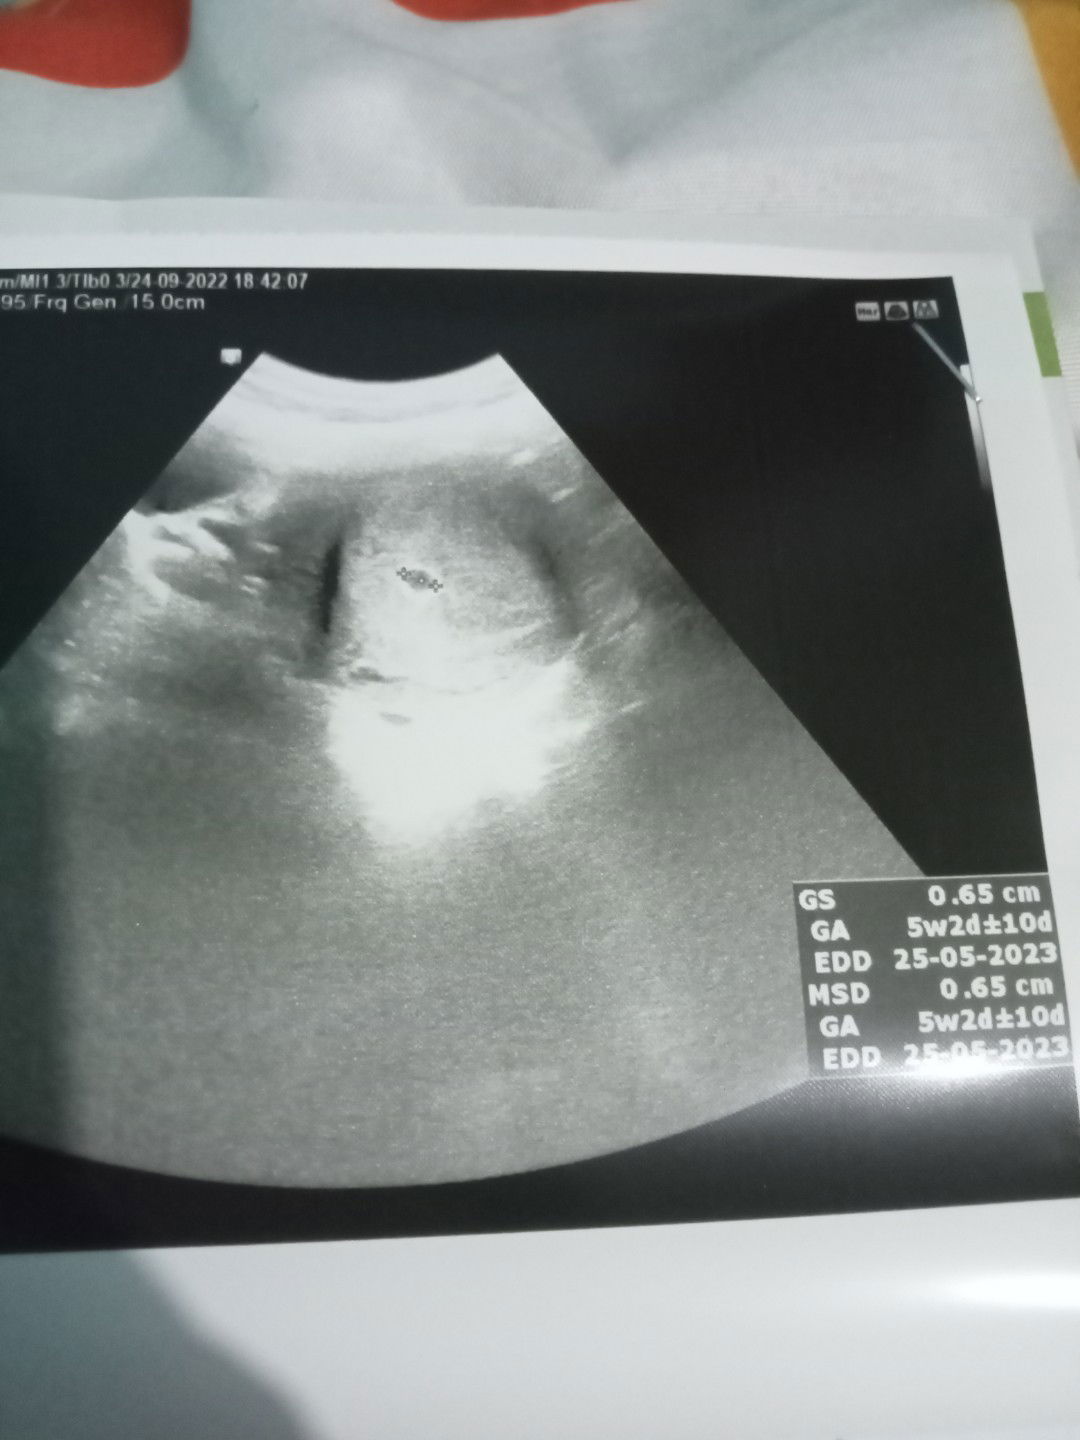

Bun , disini yg sudah cek leb di usia Kehamilan brp ya ?? Share dong

Cek Leb kehamilan